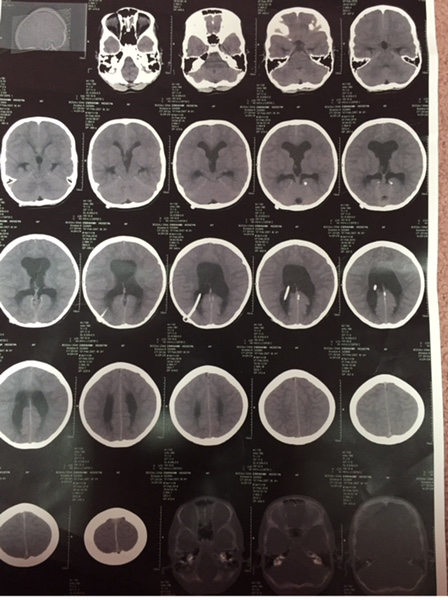

A CT scan of the head established a moderate degree of hydrocephalus by a satisfactorily situated right ventricular catheter (Figure 1). A shunt series presented a disconnection of the distal tube of the shunt (Figure 2). The distal part was free in the abdominal cavity, especially in the direction of the right inguinal canal. The shunt tube was not presented in the cervical x-ray. It appeared that the disconnection had occurred in the distal part of the shunt pump system in the neck. An abdominal and pelvic sonography did not show any evidence of mass or fluid collection or signs of infection. After urgent aspiration of the proximal valve the patient awoke quickly. Blood and CSF culture and analysis were negative for infections.

Figure 1 CT scan of the head showed moderate hydrocephalus due to a satisfactorily situated right ventricular catheter.